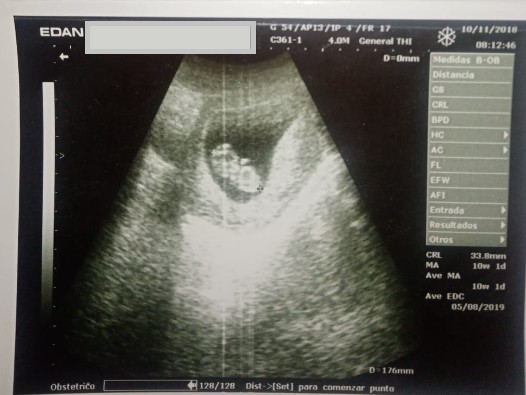

The mother attended seven prenatal checkups, undergoing five ultrasounds, the first at 6 weeks of gestation and the second at 10 weeks (Figure 1), both of which were normal. The following ultrasounds reported difficulty in observing fetal limbs.

Ultrasound at 6 weeks of gestation, with no apparent pathologies.